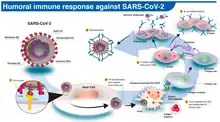

- "It's a very complicated receptor binding process compared to most virus spike proteins," Benton said. "Flu and HIV have a more simple activation process." The coronavirus is covered in spike proteins, and it's likely only a small fraction of them go through these conformational changes, bind to human cells and infect them, Benton said.

We know that the spike can adopt all these states that we were talking about," said co-lead author Antoni Wrobel, who is also a postdoctoral research fellow at the Francis Crick Institute's Structural Biology of Disease Processes Laboratory. "But whether each of the spikes adopts all of them we can't say because we can see only kind of snapshots."

The spike protein is very quick to change. In the lab, the spike can morph into all of these different conformations in less than 60 seconds, Wrobel told Live Science. But "this will be very different in a real infection; everything will be slower because the receptor will be stuck on the surface of a cell so you have to allow time for the virus to diffuse to this receptor," Benton said.

Why does the spike protein go through this many conformational changes to infect a cell? It "may be a way of the virus protecting itself from recognition by antibodies," Benton said. When the spike protein is in its closed states, it hides the site that binds with the receptor, maybe to avoid antibodies coming in and binding to that site instead, he said.- Donald Benton and Antoni Wrobel as quoted by Yasemin Saplakoglu in ”Coronavirus spike protein morphs into 10 different shapes to invade cells”, Live Science, (September 28, 2020)

The origin of SARS-CoV-2 is still an open question (see ‘Family of killers’). The virus shares 96% of its genetic material with a virus found in a bat in a cave in Yunnan, China4 — a convincing argument that it came from bats, say researchers. But there’s a crucial difference. The spike proteins of coronaviruses have a unit called a receptor-binding domain, which is central to their success in entering human cells. The SARS-CoV-2 binding domain is particularly efficient, and it differs in important ways from that of the Yunnan bat virus, which seems not to infect people5.

But although genetic material from the virus is showing up in these various tissues, it is not yet clear whether the damage there is being done by the virus or by a cytokine storm, says Wendtner. “Autopsies are under way in our centre. More data will come soon,” he says. - SARS-CoV-2 is uniquely equipped for forcing entry into cells. Both SARS-CoV and SARS-CoV-2 bind with ACE2, but the receptor-binding domain of SARS-CoV-2 is a particularly snug fit. It is 10–20 times more likely to bind ACE2 than is SARS-CoV9. Wendtner says that SARS-CoV-2 is so good at infecting the upper respiratory tract that there might even be a second receptor that the virus could use to launch its attack.

- Scientists think that the involvement of furin could explain why SARS-CoV-2 is so good at jumping from cell to cell, person to person and possibly animal to human. Robert Garry, a virologist at Tulane University in New Orleans, Louisiana, estimates that it gives SARS-CoV-2 a 100–1,000 times greater chance than SARS-CoV of getting deep into the lungs. “When I saw SARS-CoV-2 had that cleavage site, I did not sleep very well that night,” he says.